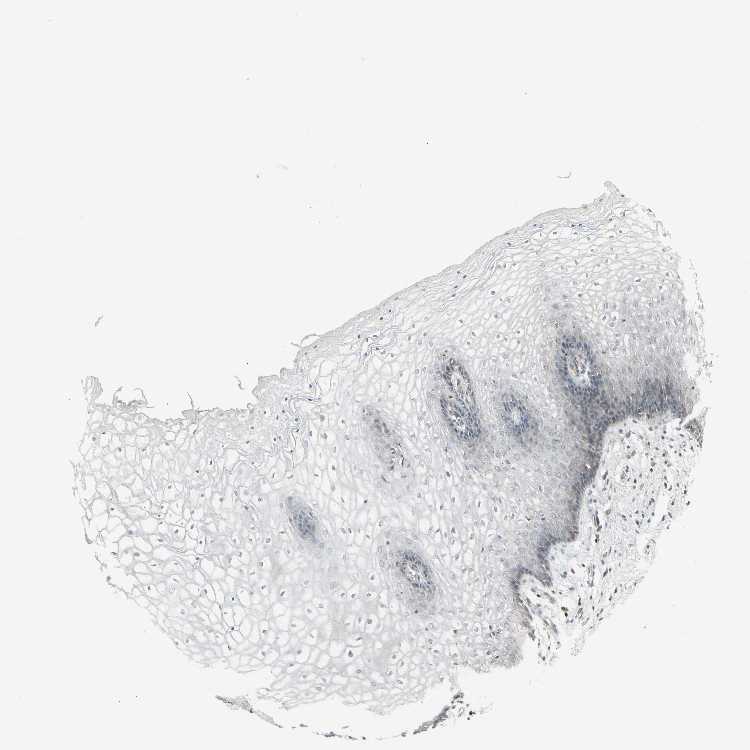

TISSUE PRIMARY DATA VAGINA Show tissue menu

VAGINA - Antibody stainingi

Antibody staining in the annotated cell types in the current human tissue is reported as not detected, low, medium, or high, based on conventional immunohistochemistry profiling in selected tissues. This score is based on the combination of the staining intensity and fraction of stained cells.

Each image is clickable and will lead to virtual microscopy that enables deeper exploration of all samples and also displays staining intensity scores, fraction scores and subcellular localization as well as patient and tissue information for each sample.

Antibody HPA008005Antibody HPA075088

Squamous epithelial cells LowNot detected